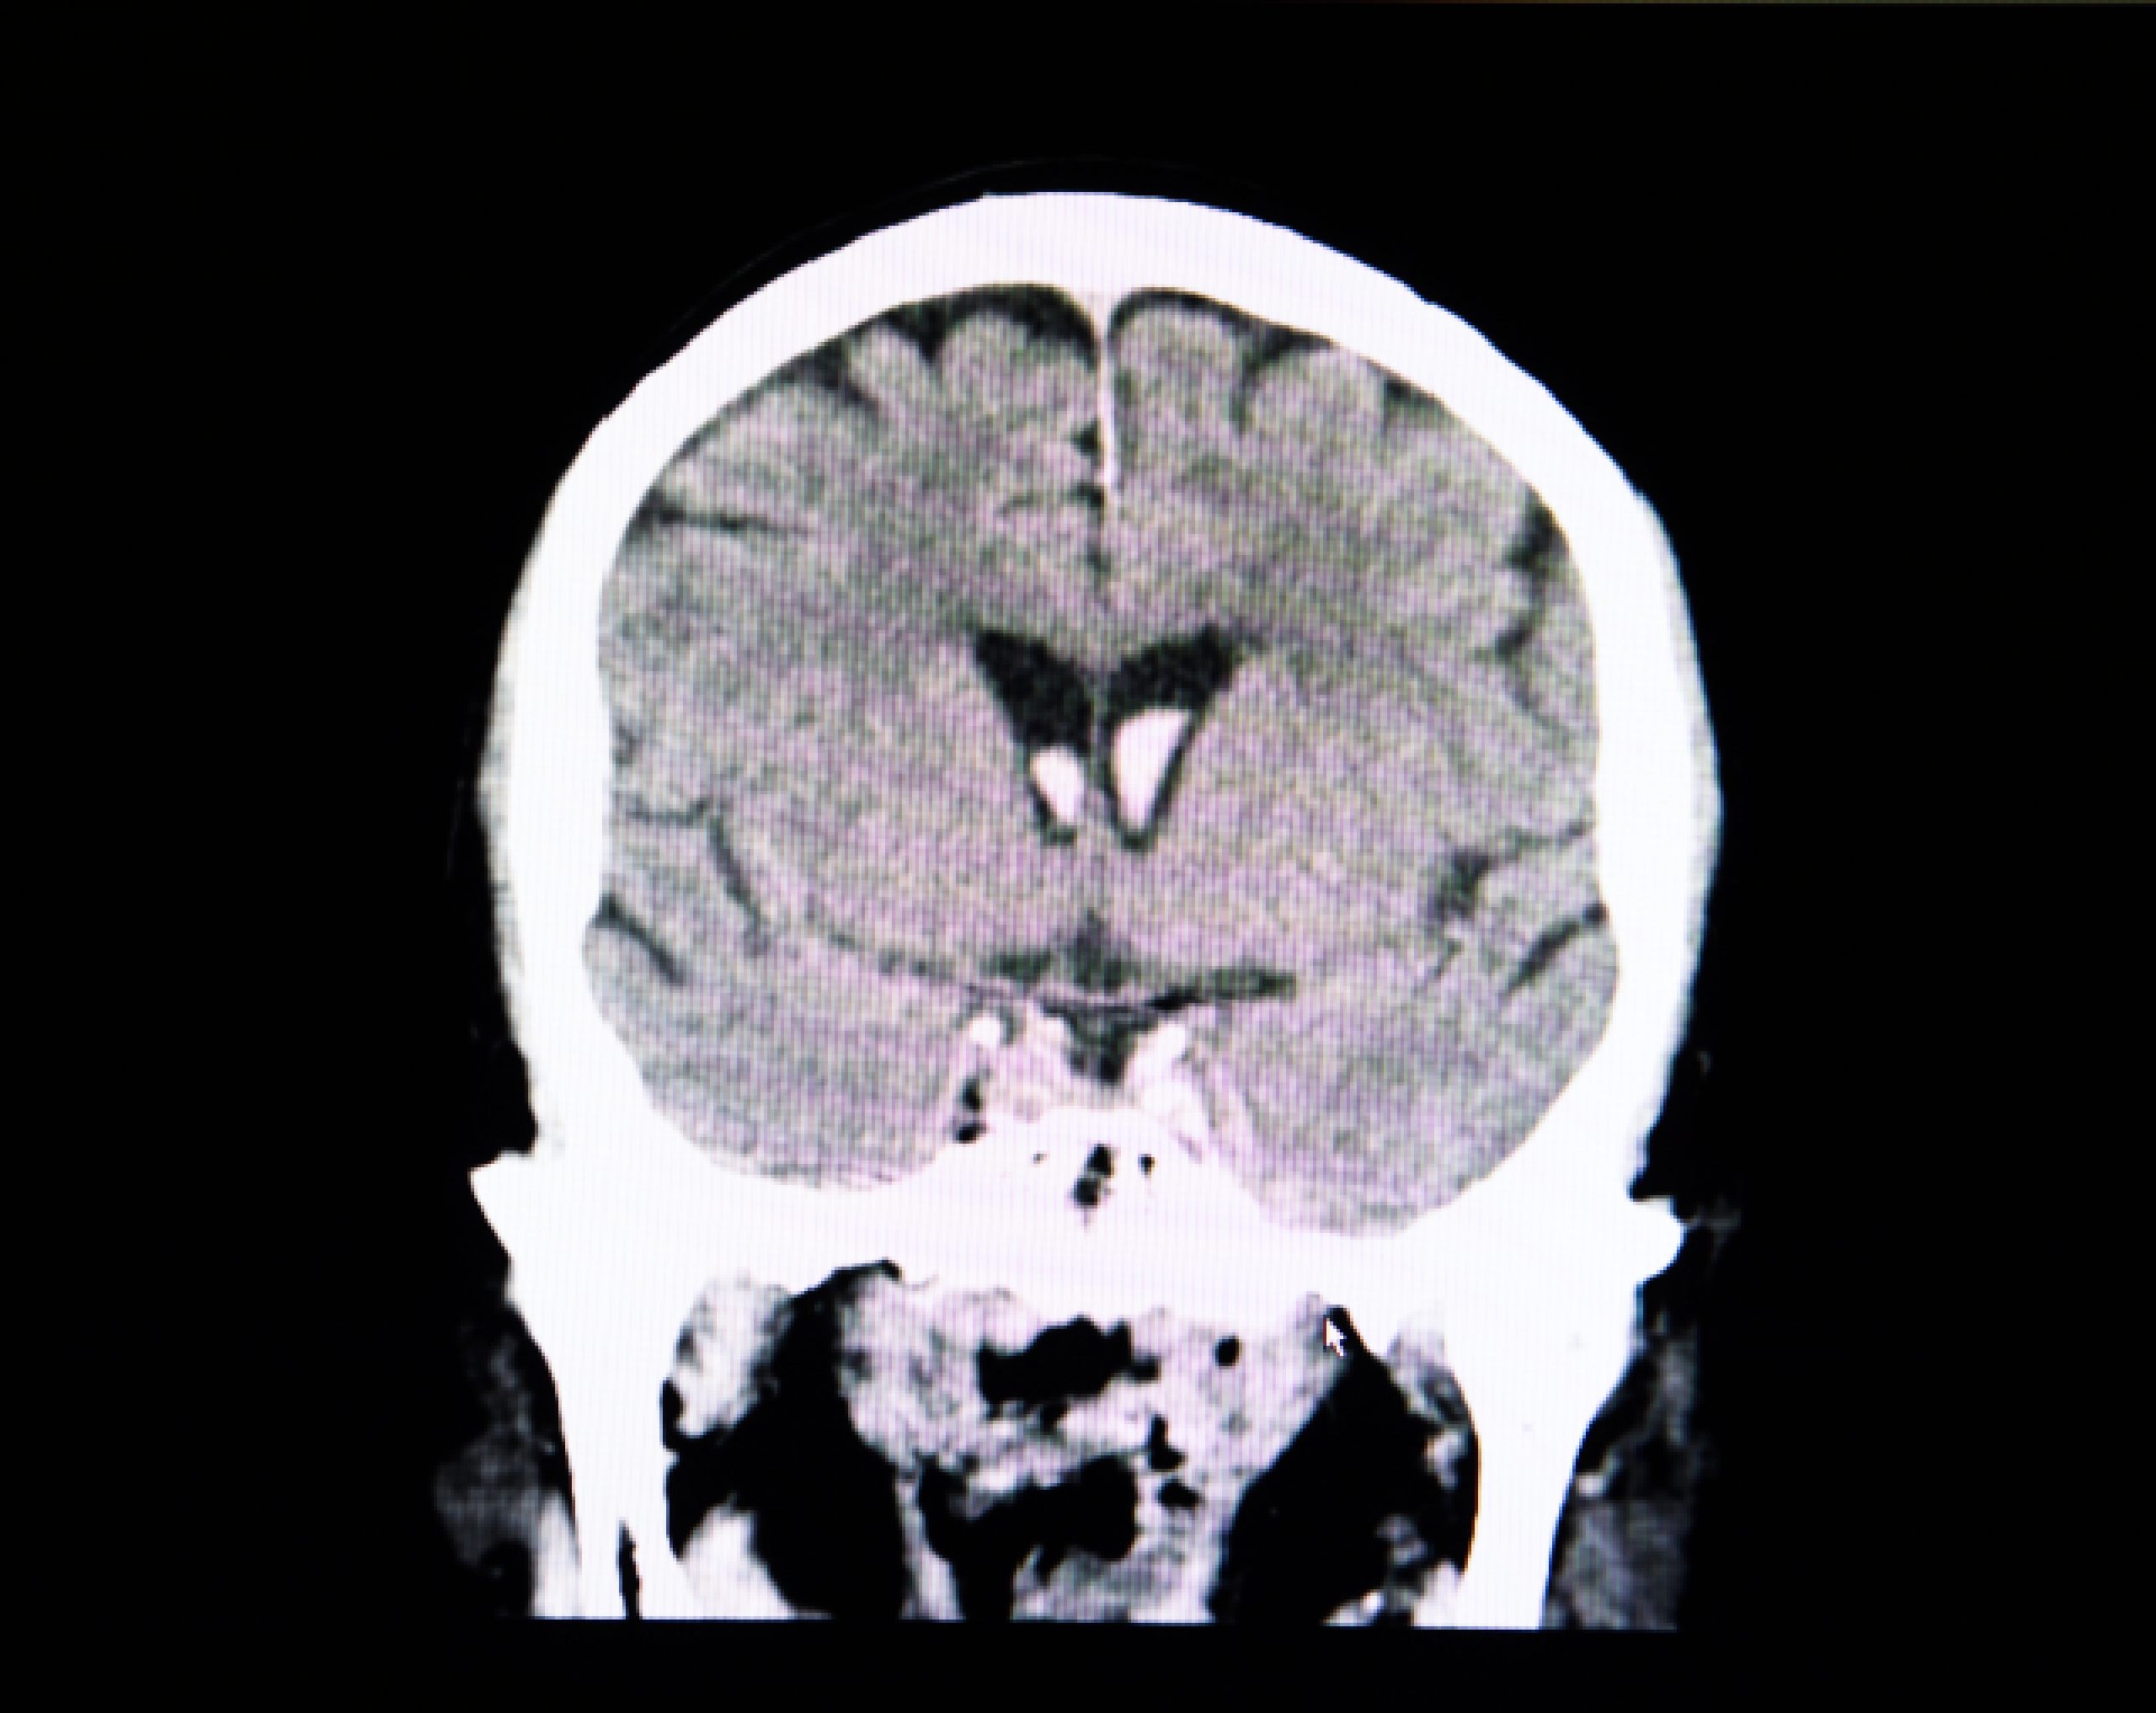

La craneotomía es una cirugía que consiste en realizar una apertura controlada en el cráneo para acceder al cerebro. Durante el procedimiento, el neurocirujano retira temporalmente una pequeña porción del hueso craneal, llamada colgajo óseo, que se vuelve a colocar al finalizar la intervención.

Gracias a técnicas avanzadas de imagen y precisión quirúrgica, este procedimiento permite tratar áreas específicas del cerebro con la mayor seguridad posible.

El principal beneficio de una craneotomía es que permite acceder directamente al cerebro para tratar condiciones que, de otra forma, pondrían en riesgo la vida o la función neurológica del paciente. Además, con el uso de tecnología avanzada como la neuronavegación o la monitorización intraoperatoria, los procedimientos son cada vez más precisos y menos invasivos.